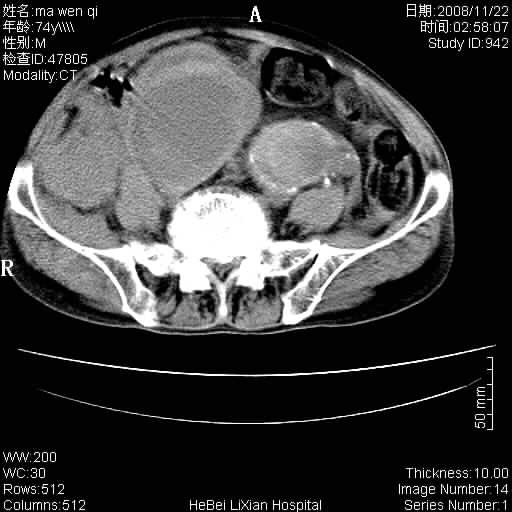

患者男 74岁.突然昏迷,休克6小时.血压70/30,头颅ct未见异常,既往体健.

腹主动脉、双侧髂动脉夹层动脉瘤破裂出血进入腹腔。

1)考虑双侧髂动脉瘤并右侧动脉瘤破裂出血,右侧腹膜后及腹腔积血。2)双侧腹股沟疝。

支持(1)双侧髂动脉瘤并右侧动脉瘤破裂出血,右侧腹膜后及腹腔积血。(2)双侧腹股沟疝。

1)考虑,腹主动脉、双侧髂动脉夹层动脉瘤破裂伴右侧腹膜后及腹腔积血。2)双侧腹股沟疝。

1)考虑胸、腹主动脉、双侧髂动脉瘤并右侧动脉瘤破裂出血,右侧腹膜后及腹腔积血。2)双侧腹股沟疝。